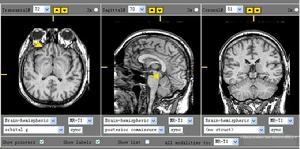

2.CT 松果體細胞瘤多呈邊界清楚的類圓形病灶,等或等高混雜密度有散在的鈣化,發生室管膜下轉移時可見腦室周圍帶狀略高密度的病灶。生殖細胞瘤邊界不規則,有時呈蝴蝶狀,多有彈丸狀鈣化,有的可見側腦室內播散,可以此確診,如圖2所示。畸胎瘤含有脂肪、骨骼及牙齒故多呈混雜密度,有低於腦脊液密度的脂肪密度區和接近骨質密度的高密度區。MRI:對腫瘤的周圍結構顯示較好,有信號不均及強化明顯的特徵(圖3)。